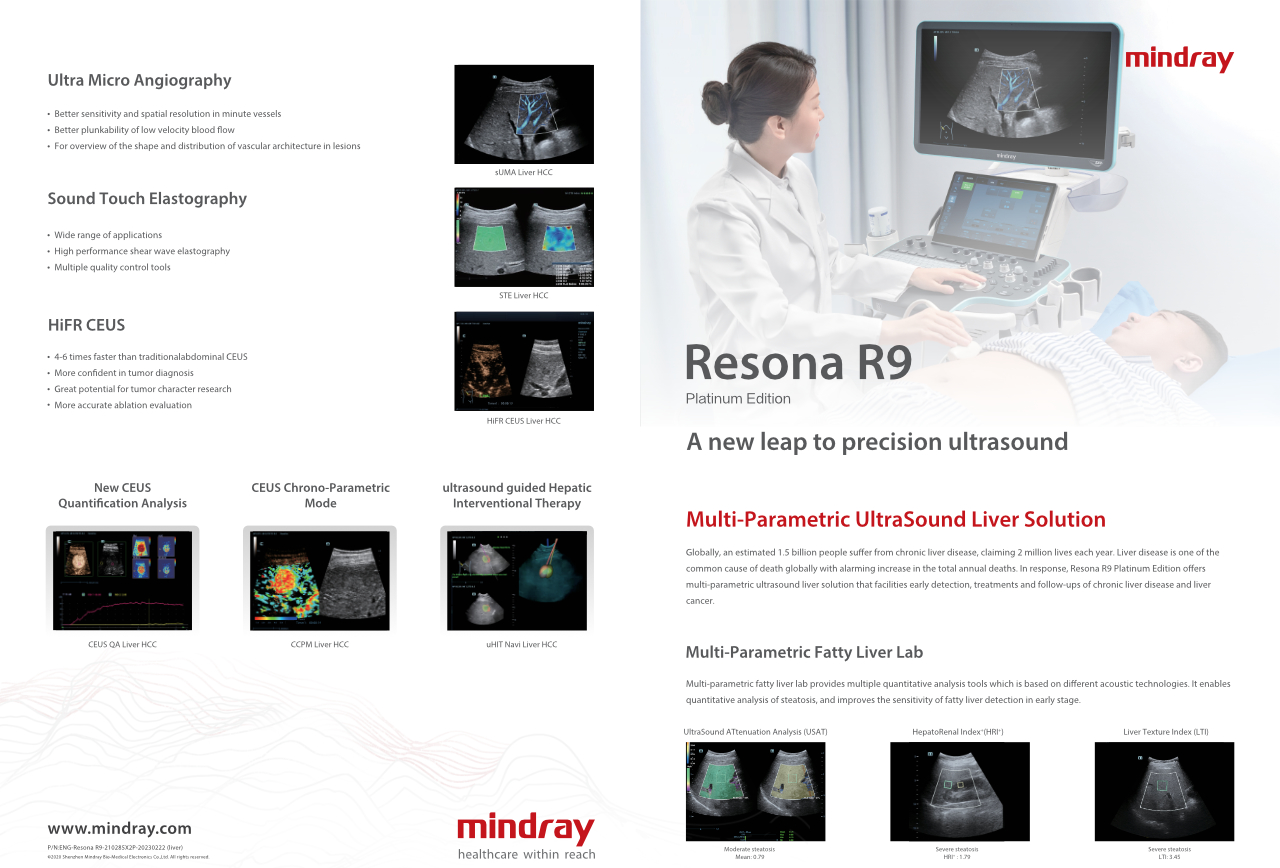

Wie deutlich k?nnen Sie eine Leber erkennen?

Bei fokalen Leberl?sionen wie H?mangiomen oder Leberkrebs spielt die Ultraschallkontrastdarstellung eine zentrale Rolle. Mit der weitreichenden nichtlinearen UWN+Kontrast-Bildgebungstechnologie k?nnen eine bessere Penetration, ein h?heres Kontrast-Gewebe-Verh?ltnis, eine geringere MI und eine l?ngere Beobachtung der Durchblutungsdauer erreicht werden.